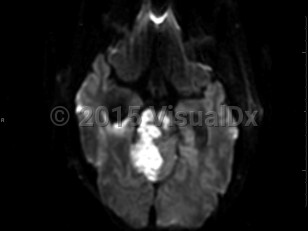

A brain stem stroke involves the brain stem, which is composed of the midbrain, pons, and medulla oblongata. Symptoms are typically acute in onset and depend on the location of injury but may include cranial nerve dysfunction resulting in eye movement abnormalities, diplopia, facial weakness or sensory loss, vertigo or dizziness, dysarthria, dysphagia, and/or tongue deviation. There may be decreased level of consciousness, abnormal breathing, nausea, body weakness, imbalance, or coordination problems as well. There are several named syndromes characterized by location of the stroke and resulting symptoms; locked-in syndrome is the most serious. Prognosis depends on the location and size of the stroke as well as timely evaluation and treatment. The brain stem gets its blood supply largely from the posterior circulation (vertebrobasilar system) with little collateral supply.